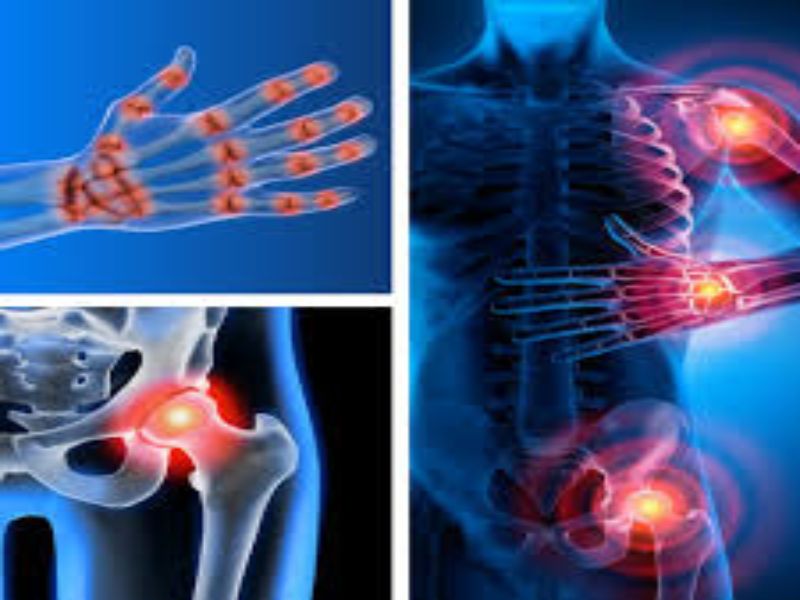

Cuando algunos de estos cartílagos sufren alguna lesión, se genera dolor, rigidez y sobre todo incapacidad funcional. Comúnmente la artrosis se encuentra en la columna cervical y lumbar de los seres humanos, algunas de las veces también se pueden localizar en los hombros y los dedos de las manos. En las caderas, rodillas y rara vez en la articulación del dedo gordo del pie.

Tipos de artrosis según la zona afectada

Los tipos de artrosis dependiendo de la zona afectada en los seres humanos, se pueden mencionar las siguientes:

- Artrosis de cadera

La artrosis en las caderas se refiere al desgaste de los cartílagos de esta articulación. Este tipo de enfermedad es muy frecuente, pero no tanto como la de rodilla o de las manos. Esta puede aparecer en las personas antes de los 50 años de edad. Uno de los síntomas es el dolor, aunque también puede aparecer rigidez y deterioro de la movilidad de la misma. El dolor de este tipo de artrosis se localiza en la ingle.

- Artrosis de mano

Se produce por los desgastes de los cartílagos de las articulaciones de las manos. Esta suele generar mucho dolor, rigidez y dificultad a la hora de realizar movimiento en los dedos. Este tipo de enfermedad generalmente comienza entre los 40 y 50 años, siendo más frecuente en mujeres, aunque este tipo de artrosis puede presentarse en ambos sexos.

- Artrosis de rodilla

Las articulaciones de las rodillas la conforman el fémur, la tibia y el peroné. Este tipo de artrosis se caracteriza por el deterioro que genera el cartílago, provocando que se genere dolor con la actividad física, problemas para caminar y permanecer de pie. Esta enfermedad aparece en las personas antes de los 50 años de edad.